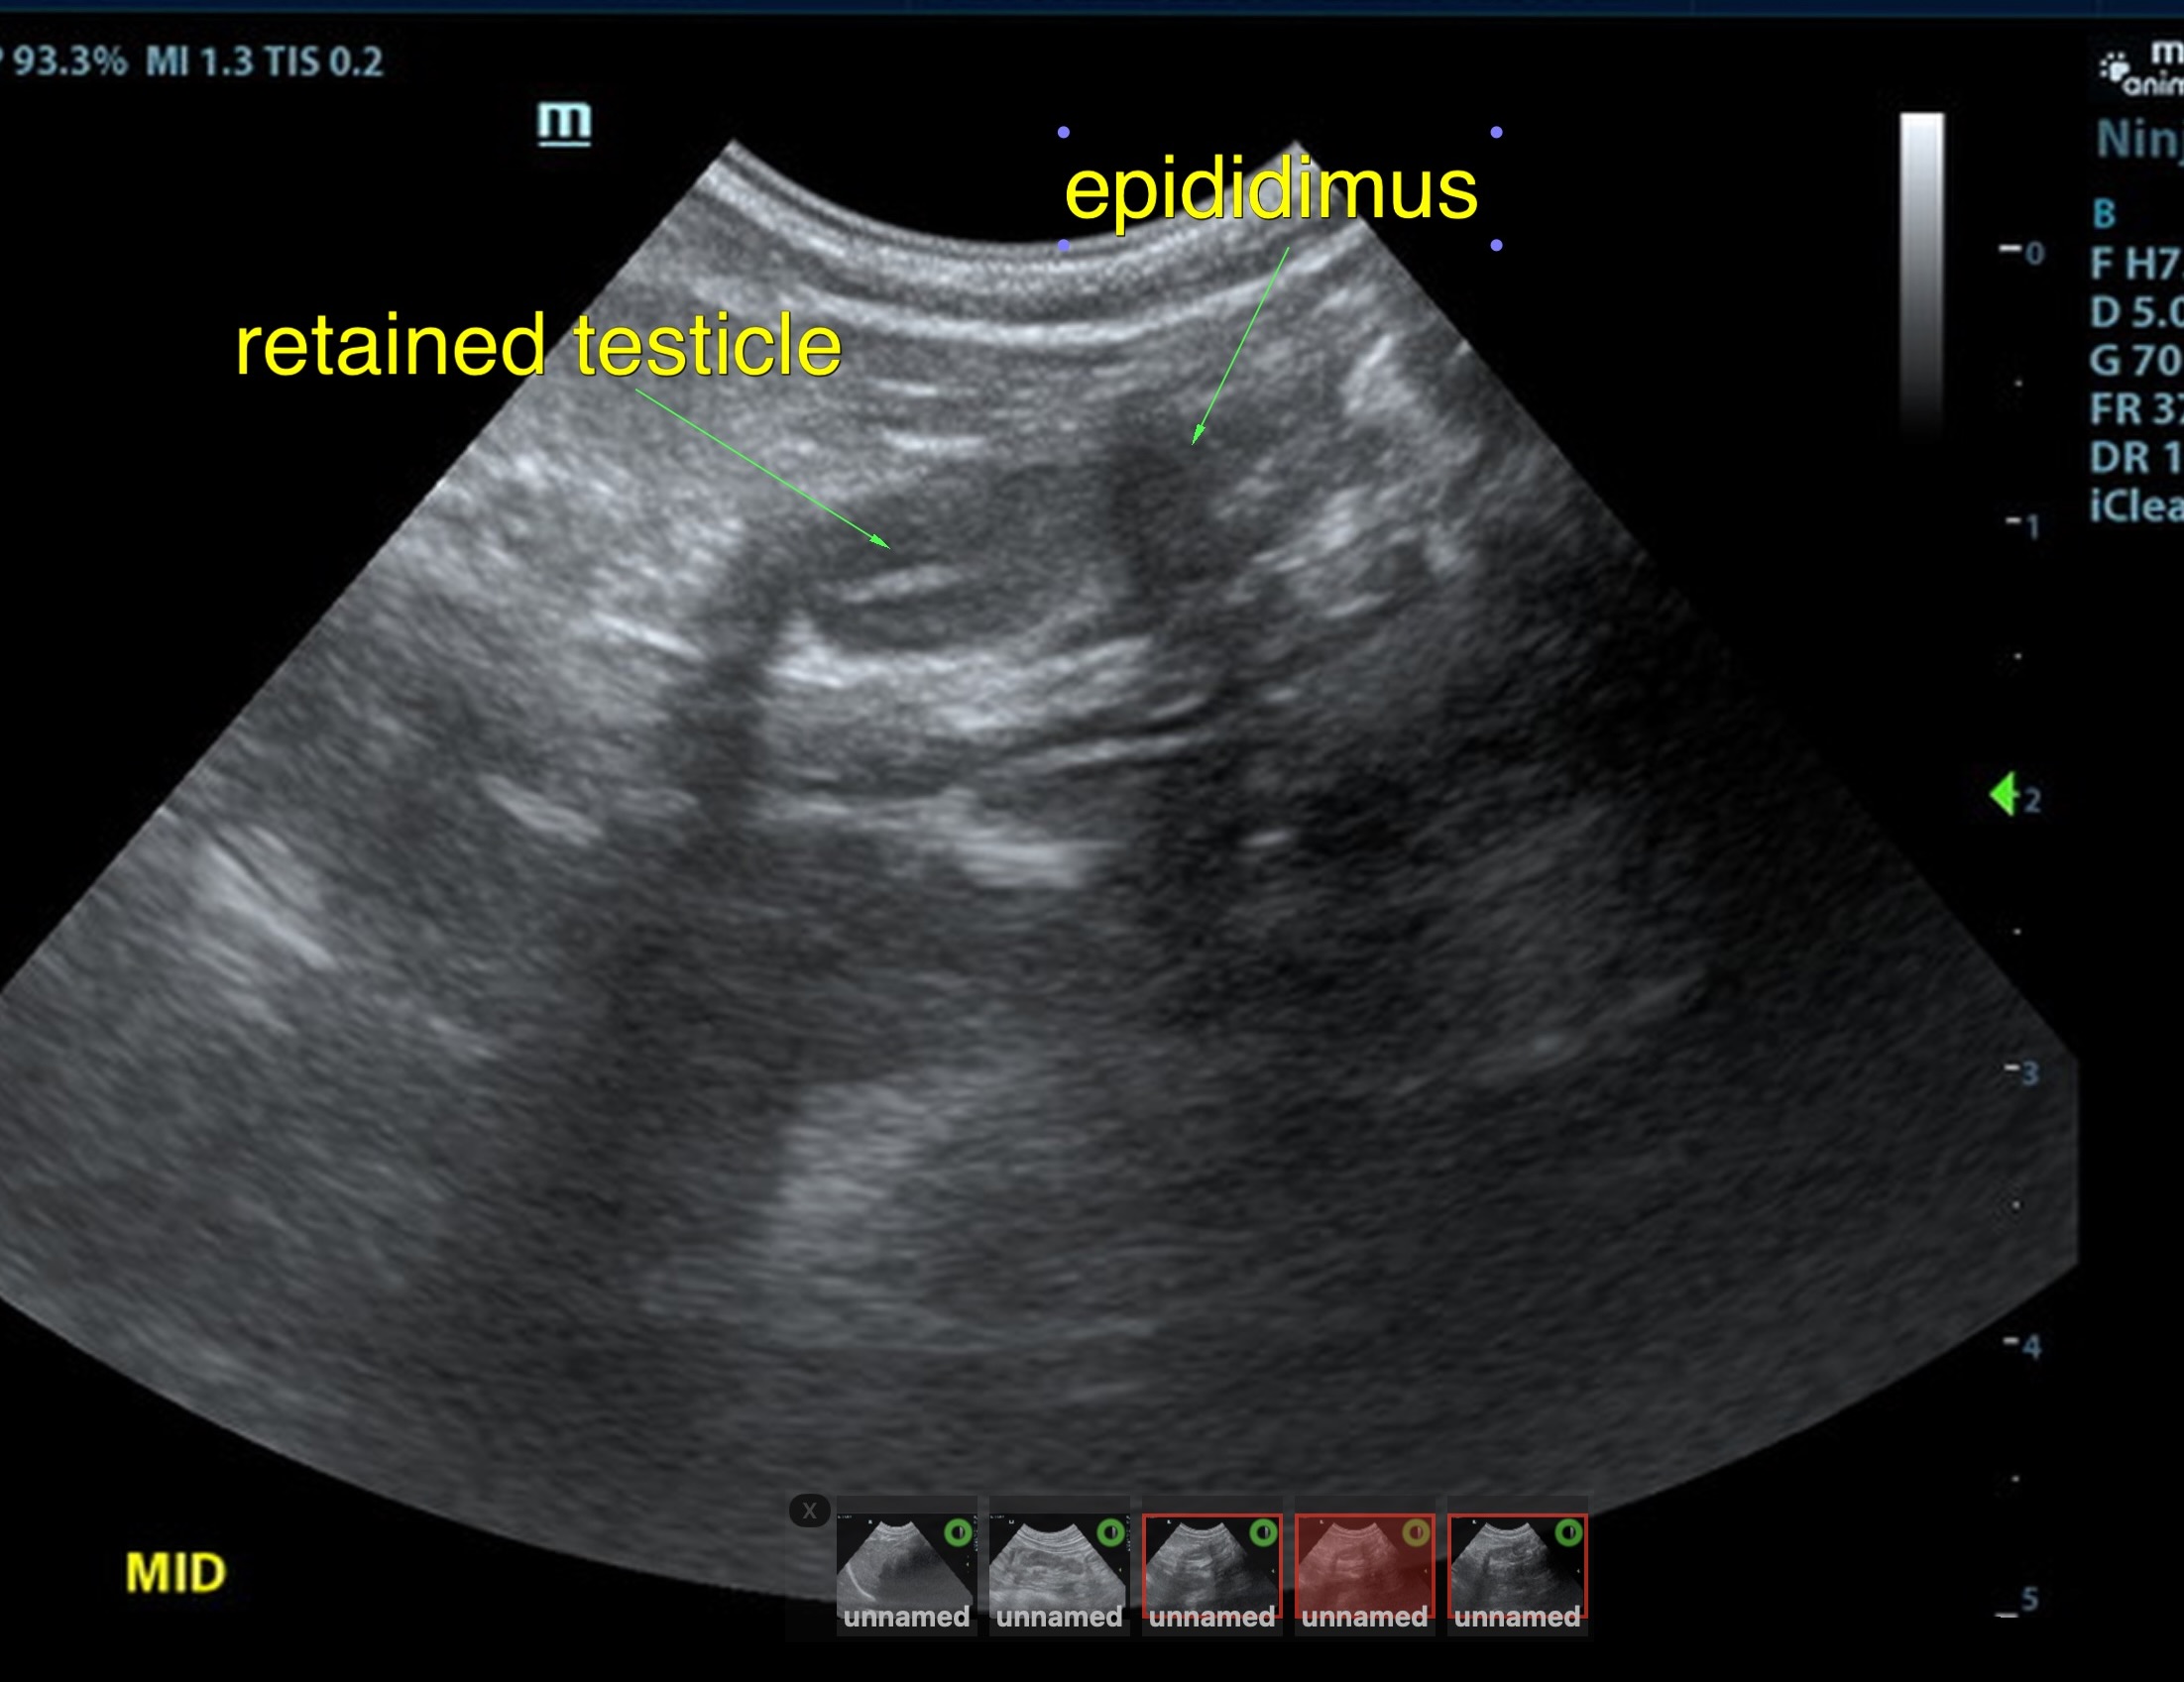

History of known unilateral cryptorchid

The retained testicle in this patient was midline subcutaneous inginal position, measuring approximately 1.6 cm in length and at a depth of 0.67 cm, approximately 2.0cm caudal from the cystourethral junction of the bladder. The left descended testicle was normal, measuring 1.8 cm

retained right testicle midline subcutaneous inguinal position

unilateral cryptorchid